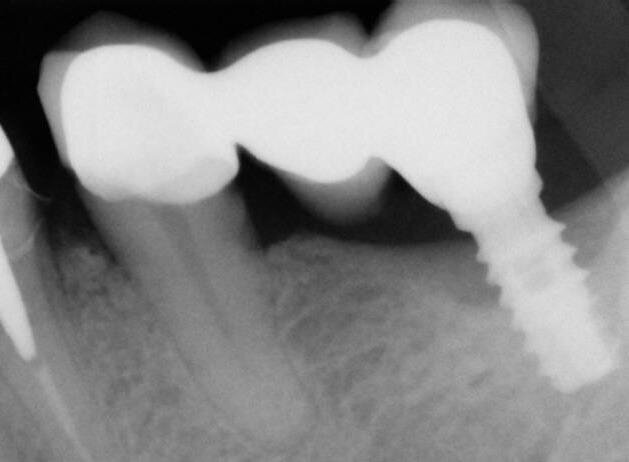

A termine del trattamento descritto in precedenza da un punto di vista clinico abbiamo ottenuto un ripristino dei parametri di salute dell’impianto ovvero la scomparsa del sanguinamento dell’edema e della purulenza, in oltre si è verificata una riepitelizzazione dei tessuti molli limitrofi l’impianto. Da un punto di vista radiografico abbiamo ottenuto la neoformazione di osso attorno alle spire dell’impianto (con relativo aumento della stabilità) che a inizio terapia era da considerarsi potenzialmente come perso. La radiografia a 60 gg prima ed a 1 anno mostrano quanto prima descritto, ovvero un ripopolamento di componenti cellulari ossei sull’impianto con un recupero di 3 spire implantari (Figg. 7-9).